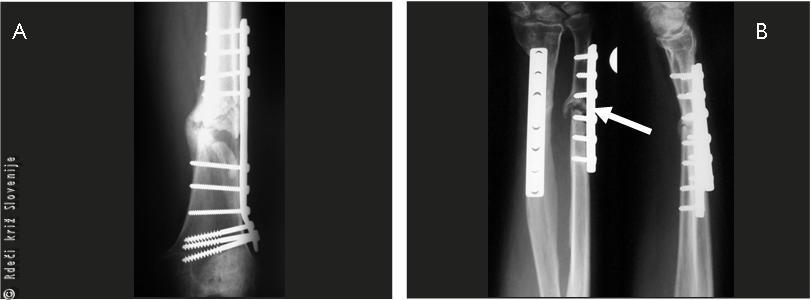

Slika 24

A – Zlom stegnenice, operiran s klasično ploščo, po 4 mesecih še ni čvrstega zaraščanja.

B – Psevdoartroza zloma podlahtnice.

Plošče, vijaki, fiksatorji in žice so tujek v telesu. Povzročajo lahko različne težave. So vstopno mesto za vnetje. Osteosintetski material lahko pritiska na žile in živce in s tem povzroča motnjo v delovanju, ali pritiska na kožo, ki lahko v prizadetem področju odmre. Omajanje vijakov in plošč preden je zlom čvrsto koščeno premoščen, je lahko posledica premalo stabilne osteosinteze, slabo prekrvljene, osteoporotične kosti, premočnega razgibavanja ali prevelike obremenitve, lahko pa tudi ponovne poškodbe. Zdravljenje je operativno. Zlom ponovno uravnamo in zamenjamo vsadek.

Slika 27

A – Po 6 mesecih je ob pretiranem obremenjevanju prišlo do zloma plošče na stegnenici.

B – 2 tedna po operaciji je prišlo do odmrtja kože, plošča je prodrla skozi kožo, prišlo je do vnetja, ki je privedlo do kroničnega vnetja.